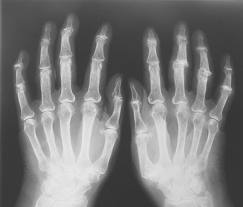

En lo que podría ser un gran avance en la aplicación práctica de la ciencia epigenética, los científicos del Reino Unido utilizan muestras de tejidos humanos para descubrir que las personas con osteoartritis tienen un cambio de la firma epigenéticos (metilación del ADN), responsable de activar y desactivar un gen que produce una enzima llamada destructiva MMP13.

Esta enzima se sabe que juega un papel en la destrucción del cartílago articular, por lo que MMP13 y los cambios epigenéticos que conducen a sus niveles más altos, los objetivos principales para el desarrollo de la osteoartritis de drogas. Además de ofrecer una vía epigenética nueva hacia una cura para la osteoartritis, la investigación también ayuda a mostrar cómo los cambios epigenéticos desempeñan un papel en las enfermedades fuera de cáncer. Este hallazgo fue publicado recientemente en línea en la revista FASEB Journal.

Para hacer el descubrimiento, Young y sus colegas compararon la medida en que la metilación del ADN es diferente en el cartílago de los pacientes que sufren de osteoartritis y las personas sanas de edad similar. Se encontró que a una pequeña posición, el gen para MMP13 tenía menos metilación del ADN en pacientes enfermos. Luego se confirmó que la metilación reducida de este gen aumenta los niveles de la enzima destructiva MMP13.